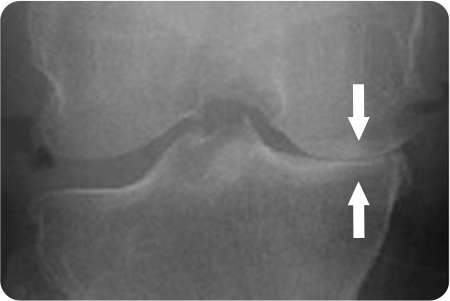

무릎 관절염

인공관절치환술

퇴행성 관절염으로 닳아버린 연골과 변형된

뼈 표면만을 정밀하게 절제합니다.

무릎의 굽힘·펴짐과 안정성을 고려해

인공관절을 삽입, 무릎 중심축을 바로 잡아줍니다.